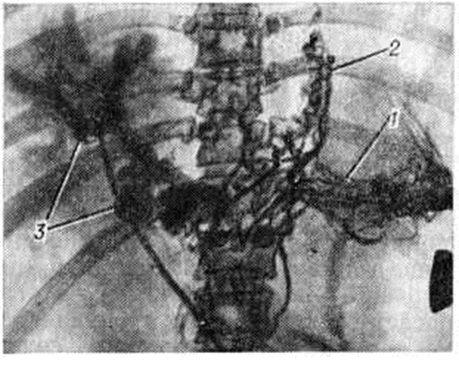

Рис. 4.

Спленопортограмма при внутрипечёночной портальной гипертензии: резко расширенное спленопортальное русло с функционирующей пупочной веной; 1 — воротная вена, 2 — селезёночная вена, 3 — расширенная коронарная вена желудка, 4 — пупочная вена.